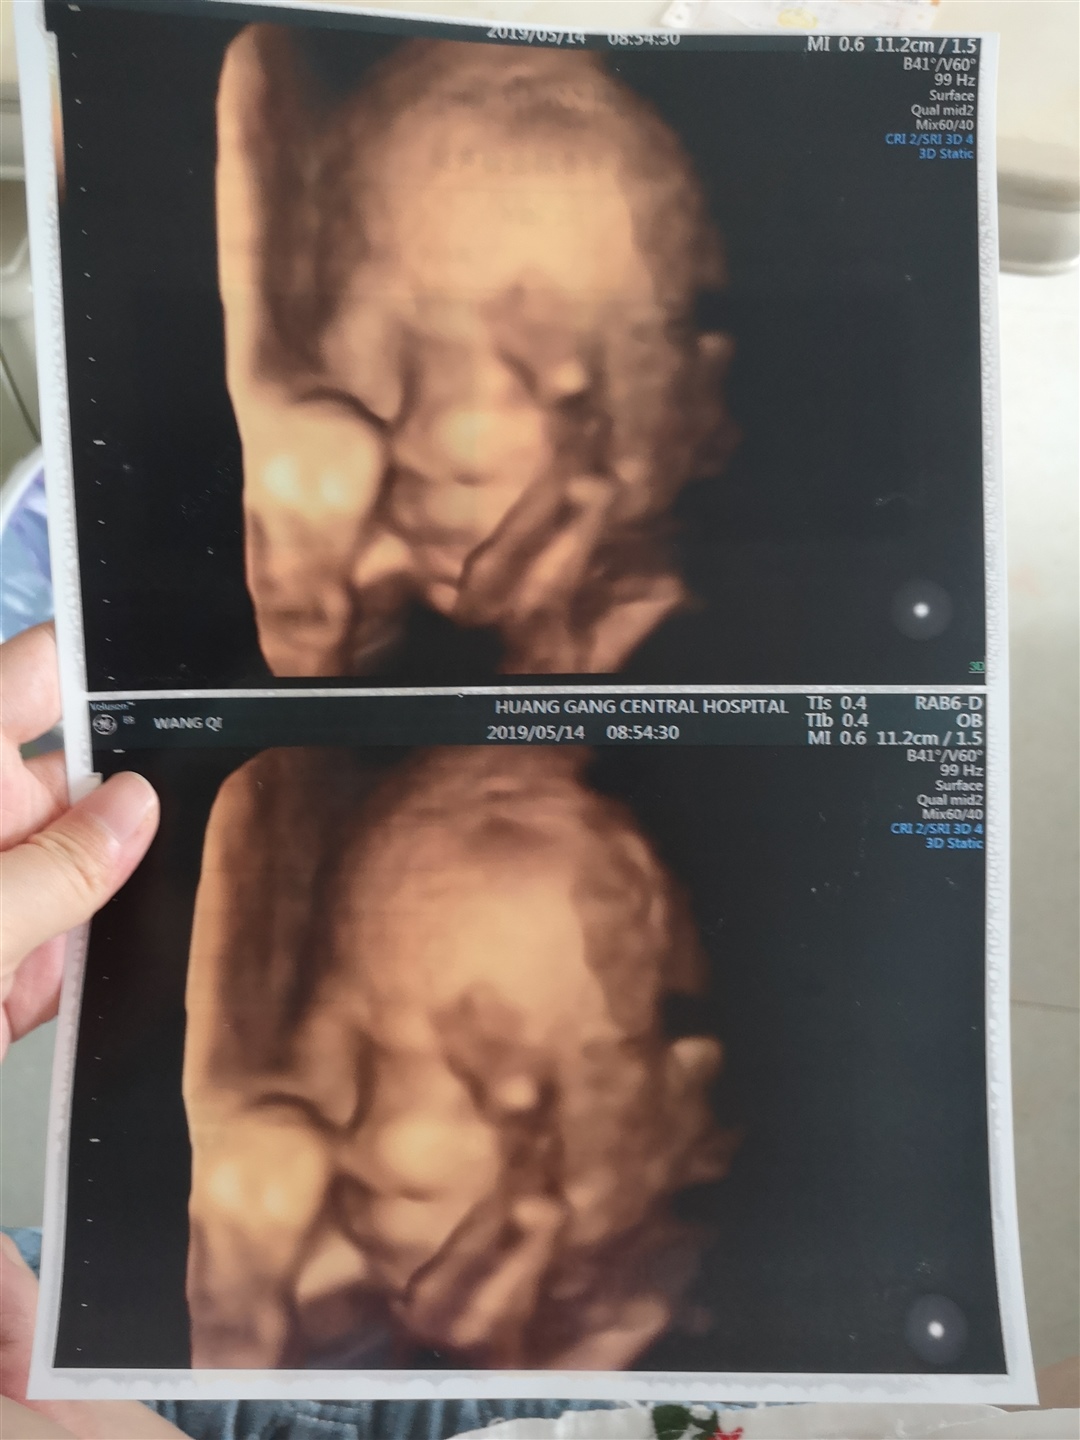

孕22周+4天